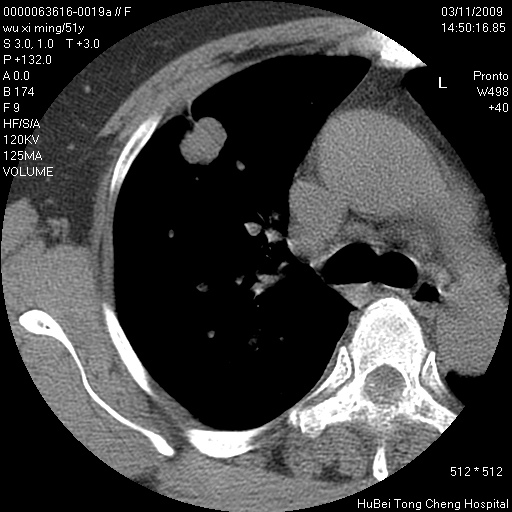

患者 女,51岁。因“胆囊炎,胆囊结石”,行常规术前胸部x线检查发现:右上肺结节病灶,建议行进一步检查。患者无咳嗽、咳痰及咯血等呼吸道症状,近期出现背部疼痛不适。

胸部ct轴位平扫(层厚10mm,螺距1.5,重建间隔10mm;部分层面:层厚3mm,螺距1.0,重建间隔3mm),图像如下:

右肺周围型肺癌伴肺内转移信胸椎转移

支持--右肺周围型肺癌---胸椎转移

支持右上肺肺癌并胸椎转移

有周围性肺癌胸椎转移

右肺周围型肺癌伴肺内转移及胸椎转移。已无手术机会。